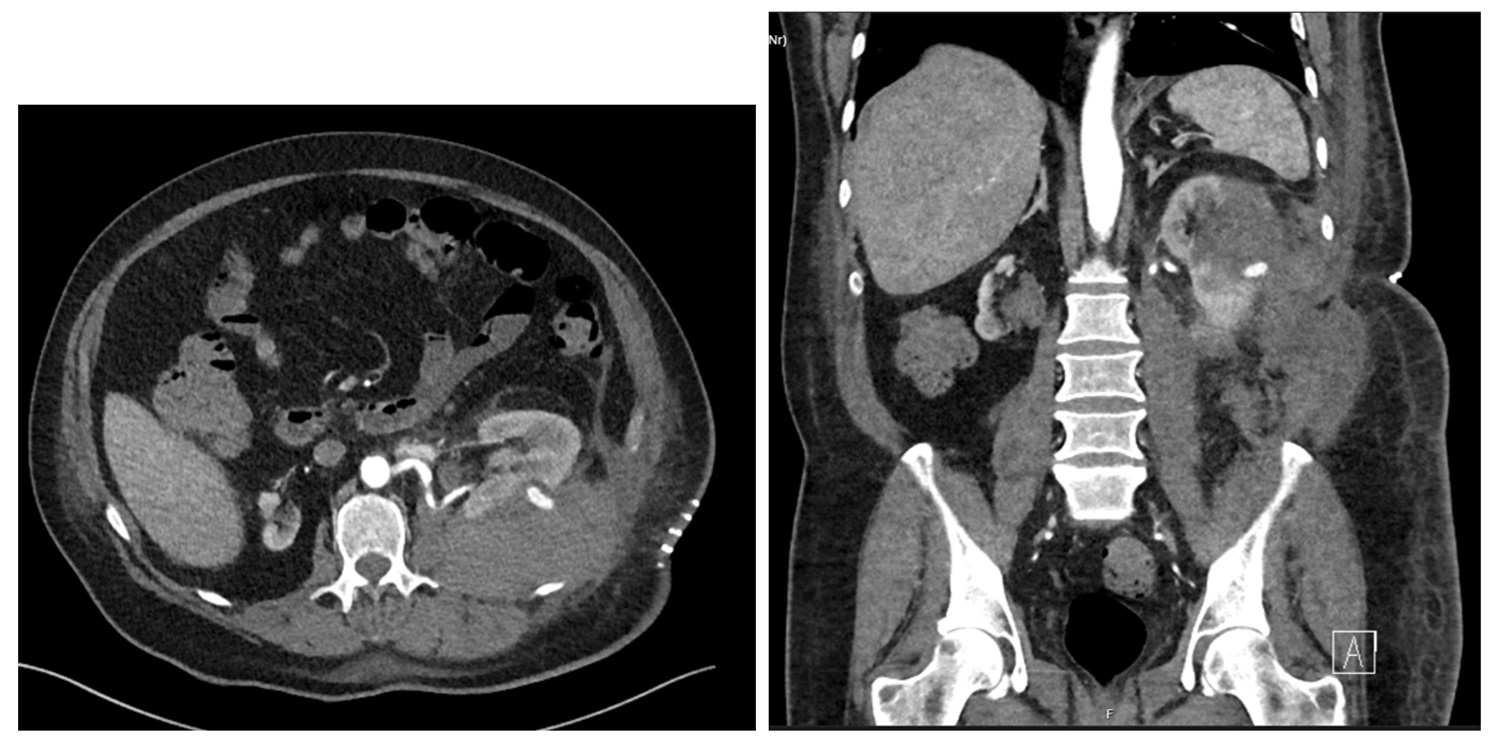

Figure 2: CT (axial and coronal) of the pseudoaneurysm and perirenal haematoma.

Ten days postoperative he presented to A&E at another hospital with tachycardia and with fluid leaking from his flank wound. Blood tests showed a Hb drop to 70 (from 100), AKI (eGFR 15), and subsequent CT showed a pseudoaneurysm extending from the posterior aspect with perinephric haematoma and haemoperitoneum (Figure 2). The collecting system was prominent. He underwent urgent angioembolisation with three microcoils injected into the two feeding vessels to the aneurysm, and was transferred to the intensive care unit (ICU). The phimosis was seen to have recurred and caused a degree of urinary retention requiring re-catheterisation.